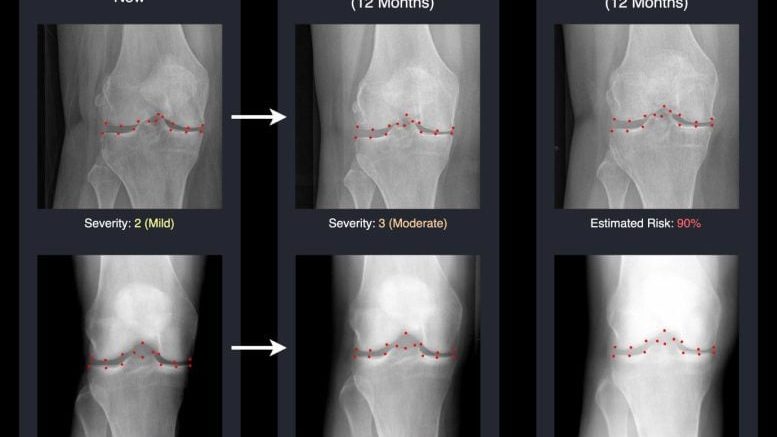

AI predicts osteoarthritis progression. Credit: University of Surrey An AI system developed at the University of Surrey can predict future knee X-rays, helping reveal how osteoarthritis may worsen over time. By turning complex predictions into…